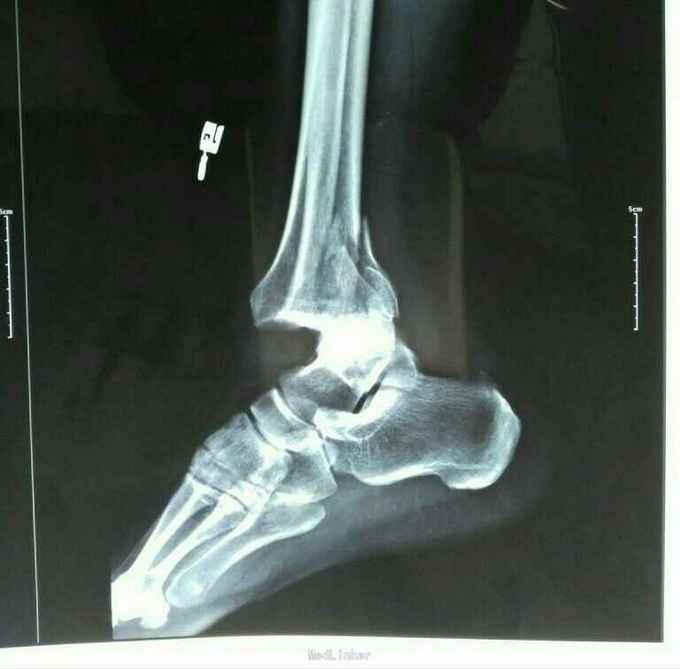

摔伤致右踝关节疼痛肿胀、活动受限3小时余 家属代述3小时前不慎摔伤致右踝关节,当即感疼痛,肿胀活动不利,未行任何治疗,急于我院就诊,经拍片查体后以右踝关节粉碎性骨折收入院。入院时,患者神志清,精神可,各项生命体征稳定,无恶心、呕吐,无头晕、头疼,纳食可,二便调。

专科检查:右踝关节压痛(+),肿胀,活动不利,可触及骨擦感,闻及骨擦音,皮下淤青,肢端感觉及血运可,足背动脉可轻微触及。 拍片示:右踝关节粉碎性骨折